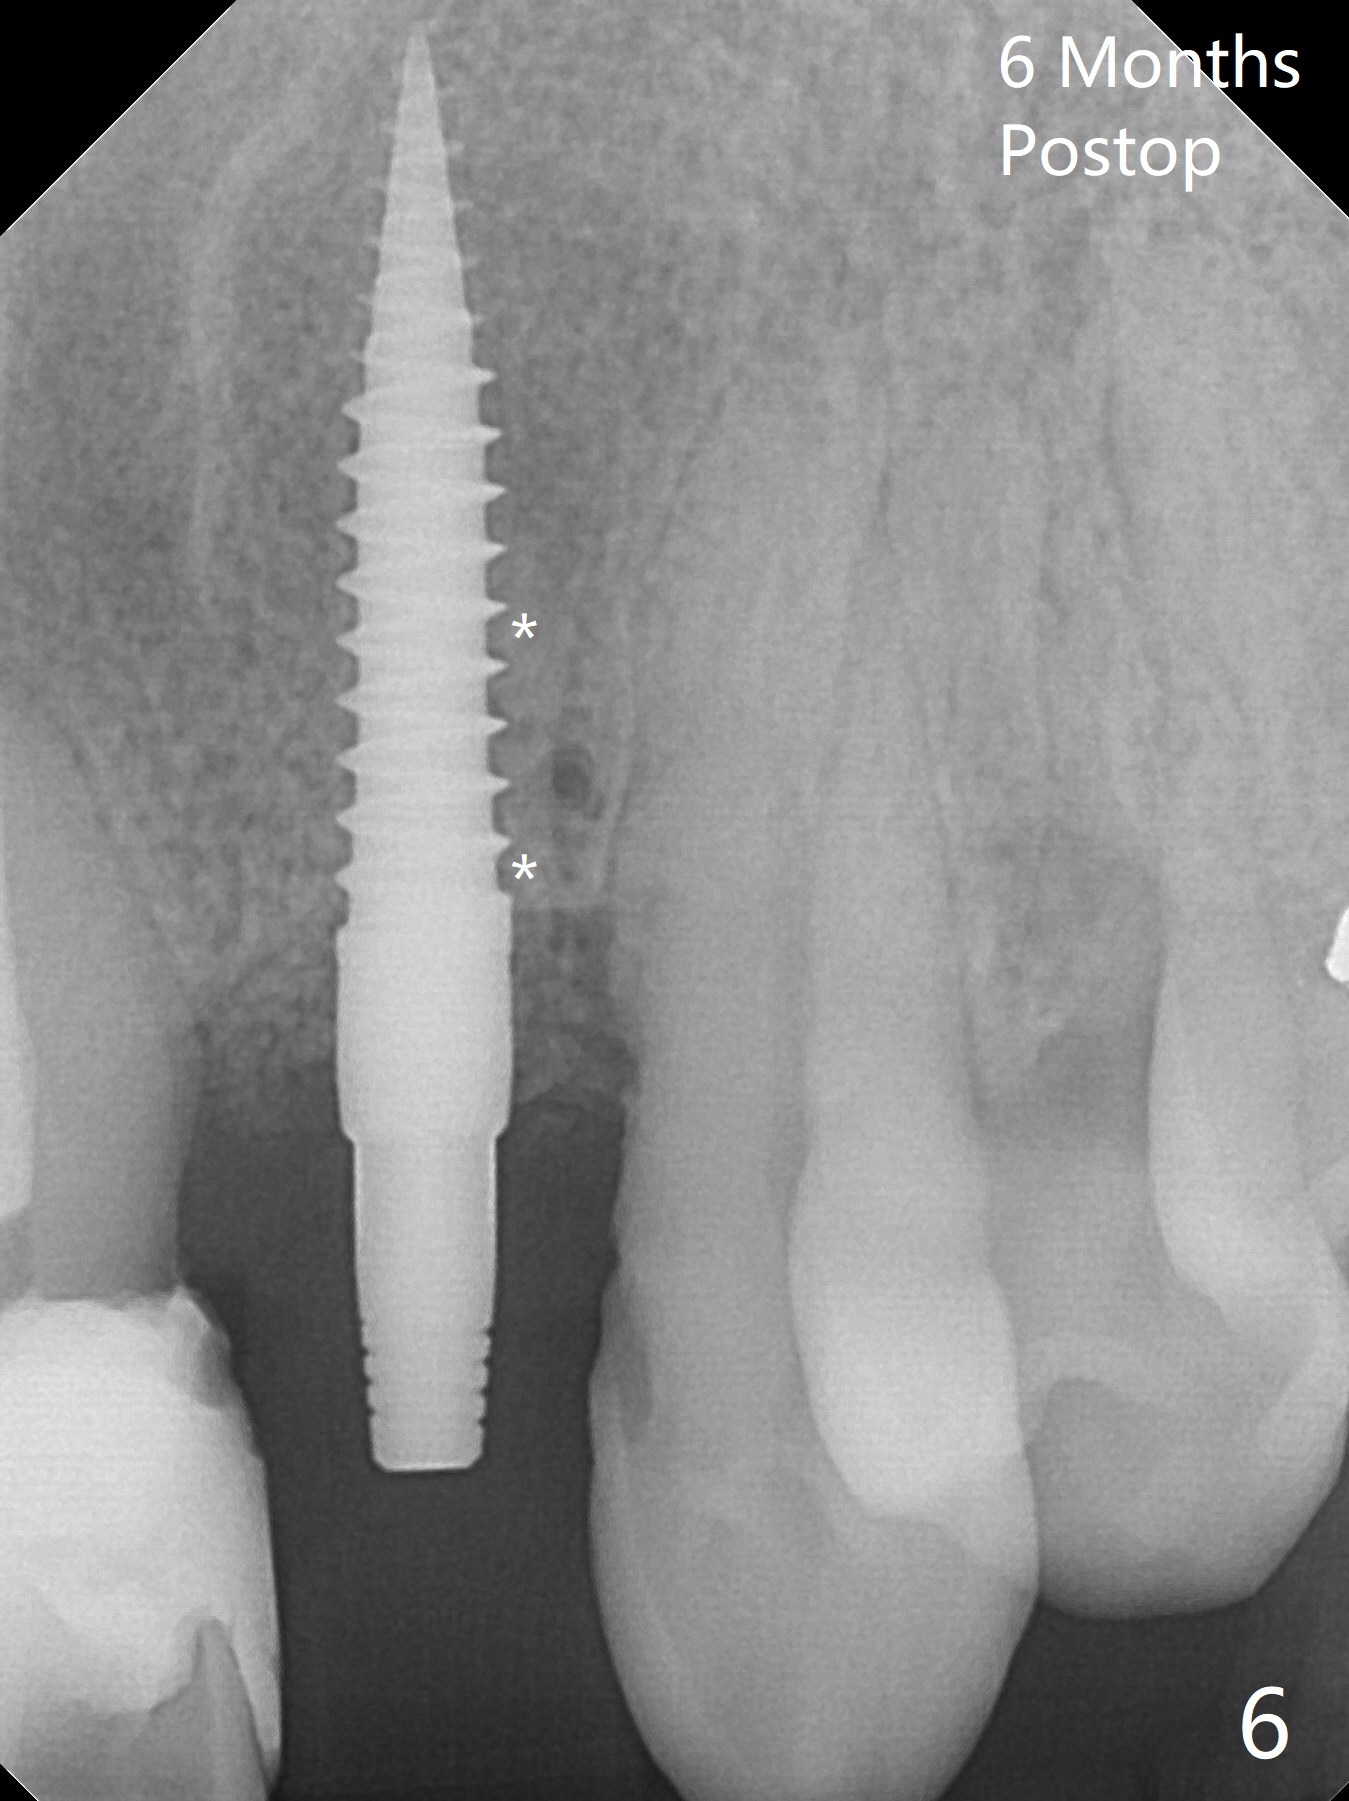

When the 67-year-old man returns for #23-26 crown/FPD cementation, the tooth #10 has fractured with necrotic pulp (Fig.1) and periapical radiolucency (Fig.2 (CT coronal section) *). He requests immediate implant since he has difficulty in getting ride from out of state. After curettage of the apical granulation tissue, a 3x16(2) mm 1-piece implant is placed with 20 Ncm because of slight overprep using 2 mm drill (Fig.3). Postop CT shows that the implant does not seem to be small (Fig.4). The fracture of the tooth #10 is related to edge-to-edge occlusion with the tooth #22 while the lower restoration is being fabricated in lab (Fig.5). It is easy to achieve occlusal clearance when the immediate provisional is fabricated with normal overjet. The density of the bone immediately next to the implant increases 6 months postop (Fig.6 *). The soft tissue also looks normal.